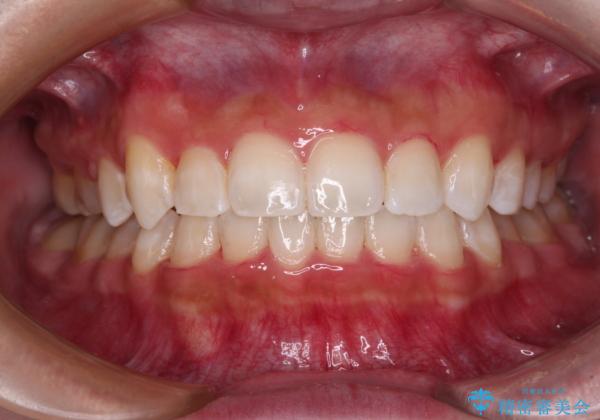

八重歯を改善 目立たないワイヤー装置での矯正治療

- 八重歯を気にして来院された患者様です。

本来であれば八重歯の隣後方の歯を抜歯するのですが、その後ろの歯が乳歯であり後続永久歯もなかったため、乳歯を抜去することとしました。

前から5番目の乳歯は、後続永久歯である小臼歯と比べて幅径が大きいため、移動に時間がかかりましたが、きれいに仕上げることができました。